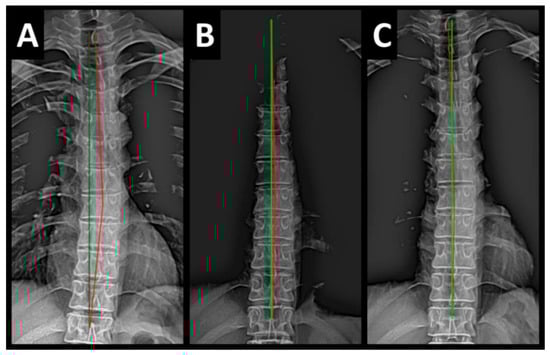

Radiography of the spine was performed with the patient upright in neutral position. Anterior–posterior (AP) and lateral films were assessed using PostureRay® digital radiographic mensuration software (Posture Co, Inc., Trinity, FL, USA) [14]. The program uses the Risser–Ferguson measurement for the AP views and the Harrison posterior tangent method (HPTM) of measurement for the lateral views. The program also compares the patient alignment of both segmental and global measurements to models of ideal spine parameters; prior studies have shown exceptionally high reliability using this system [15]. The sagittal spine absolute rotation angle (ARA) from the 2nd cervical vertebra to the 7th (ARAC2–C7) measured −18.1° (average is −34°, ideal is −42°, pain threshold is −20° [16]) (Figure 2, Figure 3, Figure 4 and Figure 5) and the AP cervical X-ray demonstrated a right lateral flexion angle relative to true vertical of the lower cervical and upper thoracic spine (cervicodorsal angle (CDA)) measuring 5.6° (ideal is 0° [16]) with a right translation of C2 with respect to T5 (TXC2–T5) measuring −17.2 mm (ideal is 0 mm). There was an increased mid-thoracic angle with a right-sided concavity from T1 to T12 (MTAT1–T12) of 9.1° (ideal is 0° [16]) with an increased translation at T8 apex of mid-thoracic angle with respect to T12 (+TXT8–T12) measuring 15.2 mm (ideal is 0 mm). There was a decreased sagittal curvature of the lumbar spine from L1 to L5 (ARAL1–L5) measuring −17.9° (ideal is −40°, average range is 35–45° [16]). The modified Ferguson pelvic radiograph demonstrated a sacral base unleveling in the frontal plane measuring −11.3 mm, being lower on the right. There was a lumbosacral angle from L1 to L5 with an L3 apex (LSA L1–L5) of −84.9° (ideal is 90°).

Post-treatment posture analysis showed improved posture (Figure 1A–C). Post-treatment radiographic examination revealed the following: improved ARAC2–C7 measuring −29.4° (vs. −18.1°); rotation around the z-axis of the thorax (RZT5) measured 1.8° (vs. normal 0°); improved -TxC2–T5 measuring −5.7 mm (vs. −17.2 mm); improved MTA T1–T12 measuring 2.1° (vs. 9.1°); improved +TxT8–T12 measuring 3.5 mm (vs. 15.2 mm); improved ARAL1–L5 measuring −25.1° (vs. −17.9°); improved sacral base unleveling in the frontal plane measuring −1.0 mm low on the left (vs. −11.3 mm low on the right); and improved LSA L1–L5 of −88.0° (vs. −84.9°) (Figure 2B, Figure 3B, Figure 4B and Figure 5B). Post-treatment RODI score was 12% (vs. 54%), indicating minimal disability. All post-treatment SF-36 scores showed improvements (Table 1). One-year follow-up posture analysis showed a maintenance of the improved posture. One-year follow-up radiographic examination revealed maintained sagittal balance and coronal spinal alignment correction improvements (Figure 2C, Figure 3C, Figure 4C and Figure 5C). One-year follow-up RODI score was 2% indicating minimal or resolved disability from baseline (54%). Post-treatment SF-36 scores showed maintained or further improved HRQoL measures reported by the patient. Long term follow-up found minimal forward head posture on the lateral posture photograph, a slight return to baseline on the A-P cervical radiograph with a right head translation measuring 7 mm. Lateral cervical radiograph assessment at long-term found the lordosis to be well maintained at 34° ARA with minimal C2-vertical anterior head translation of 6 mm. lateral lumbar radiograph showed a slight loss of lordosis at follow-up of 19°. All subjective initial symptoms were reported to be resolved at long-term follow-up. Long term follow-up SF-36 scores were the same as post-treatment with the exception of vitality, which was slightly improved (Table 1). There were no positive orthopedic or neurological tests at follow-up. The patient continued to use the ProLordotic neck exerciser at home 1–3 times per week for up to 10 min (Figure 7).

Figure 4. (AC) Pre-treatment, post-treatment, and 1-year follow-up AP thoracic radiographs. Image Features: The green line represents a normal, ideal frontal thoracic spinal alignment. The red line represents the actual frontal alignment of the T1–T12 vertebrae. The right side of the radiographs are the left side of the patient.